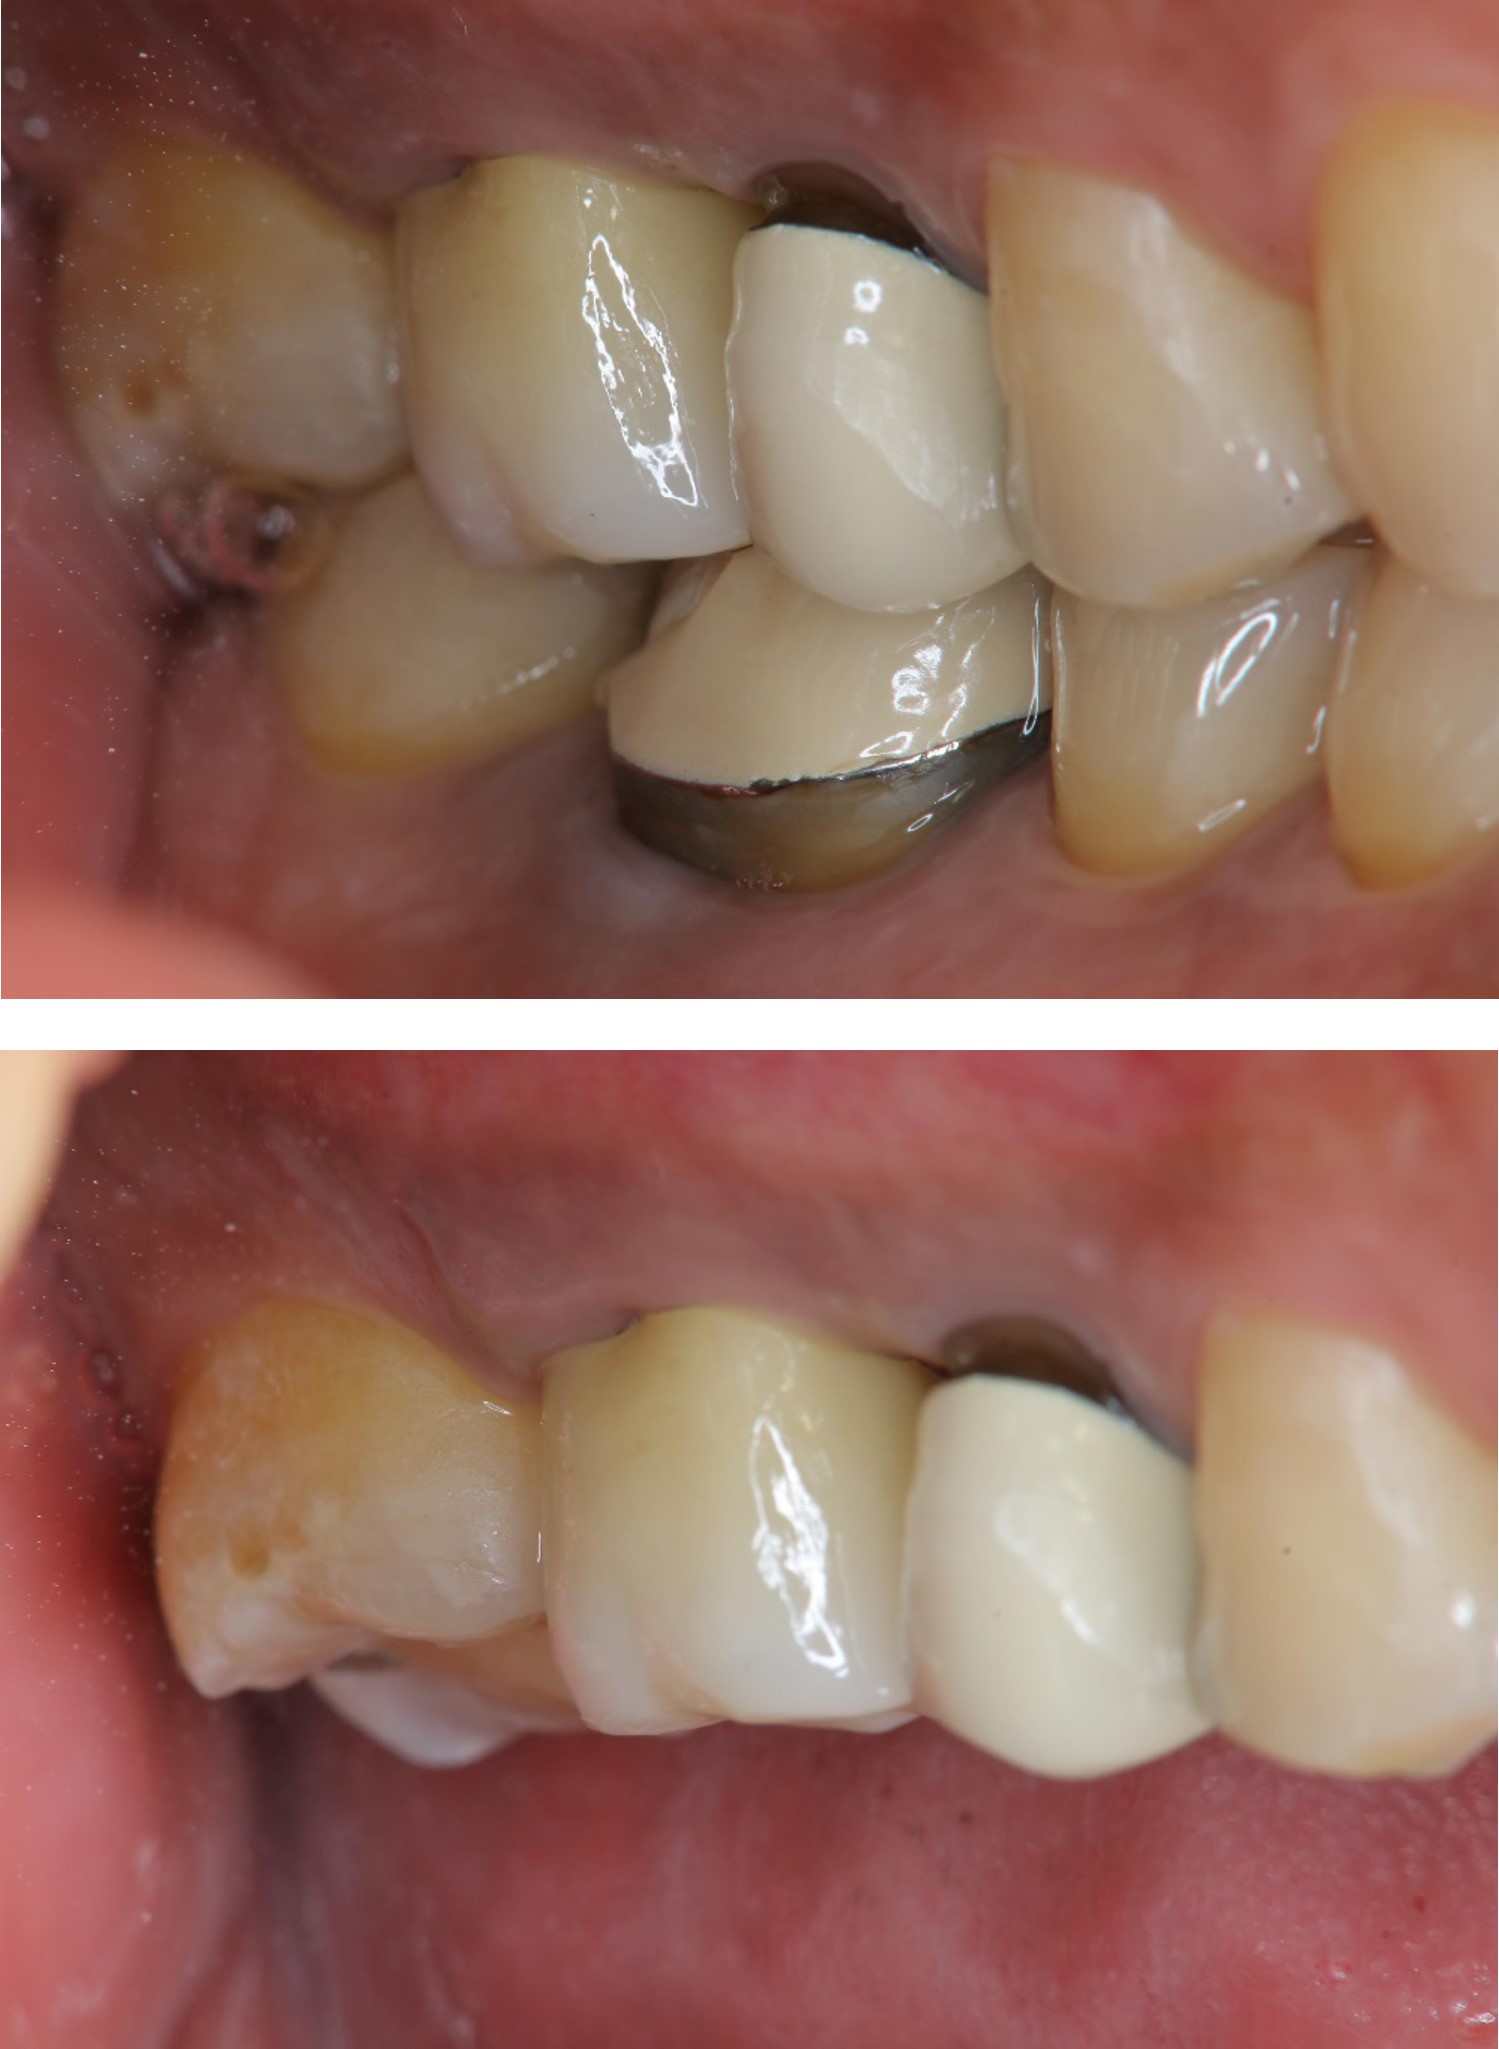

膺復前評估牙齦、牙齒狀態

治療後,咬合良好

治療後,密合度良好